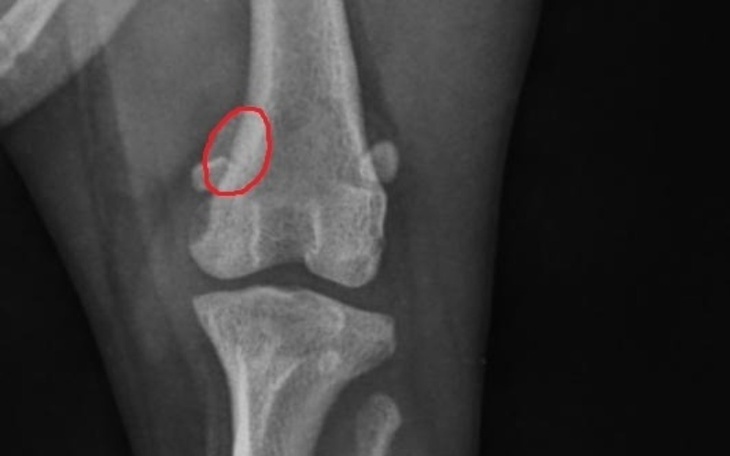

Kochani, zwracamy się do Was z prośbą o pomoc dla naszego ukochanego pieska, który niestety doznał poważnej kontuzji – zwichnął rzepkę. Ta urocza psina, która zawsze była pełna energii i radości, teraz cierpi, a każdy krok sprawia jej ból.

Rico to członek naszej rodziny, który każdego dnia wnosi do naszego życia mnóstwo miłości. Uwielbia biegać, bawić się i spędzać czas na świeżym powietrzu. Niestety, po ostatnim wypadku, każdy ruch jest dla niego wyzwaniem. Diagnoza weterynarza jest jednoznaczna – konieczna jest operacja, aby mógł znów normalnie funkcjonować i cieszyć się życiem bez bólu.